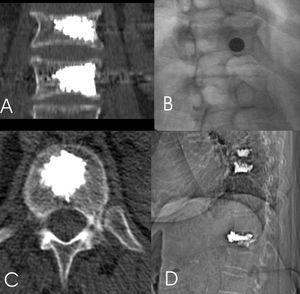

La vía de abordaje transpedicular puede ser a través de los 2 pedículos o laterotranspedicular a través de un solo pedículo (fig. 2).

Figura 2. A: acceso transpedicular; es la vía de abordaje requerida para la realización de la cifoplastia (2 accesos). B: acceso laterotranspedicular; con un trayecto oblicuo es posible acceder a la región central del cuerpo vertebral, con esta técnica se evita una punción al paciente y se acorta el tiempo del procedimiento.

Para poder realizar el acceso laterotranspedicular es necesario que la trayectoria de la aguja, para ello se inclina el haz de rayos X hasta que la apófisis espinosa se superponga con el pedículo contralateral y el pedículo a puncionar se identifique correctamente (fig. 3).